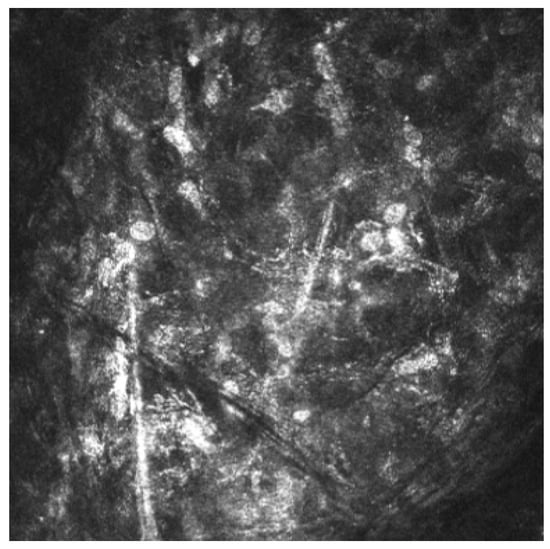

The diagnosis of AK is based on a combination of clinical suspicion, microbiological analysis (smears and cultures), polymerase chain reaction (PCR) and in vivo confocal microscopy (IVCM) [4,9]. IVCM is a noninvasive technique for corneal imaging. It enables visualization of Acanthamoeba cysts, which appear as hyperreflective, double-walled, spherical structures (15–30 µm) located in the epithelium or stroma. Hyperreflective trophozoites, which are significantly larger, are rarely observed [4,10]. The density of cysts and the depth of infiltration have been associated with disease severity [9,11,12,13].

Acanthamoeba keratitis was confirmed by in vivo corneal microscopy (Figure 4).

Control IVCM performed 90 days after the initiation of treatment did not find any Acanthamoeba cysts.

In a national survey by Jasim et al., 25% of Acanthamoeba keratitis cases were diagnosed based solely on clinical presentation due to the high false-negative rates of other diagnostic methods [20]. In vivo confocal microscopy (IVCM) is a noninvasive imaging method that has been shown in the literature to have a higher sensitivity than PCR and culture in the diagnosis of Acanthamoeba keratitis [21].

Figure 4. Acanthamoeba cysts in corneal in vivo microscopy.